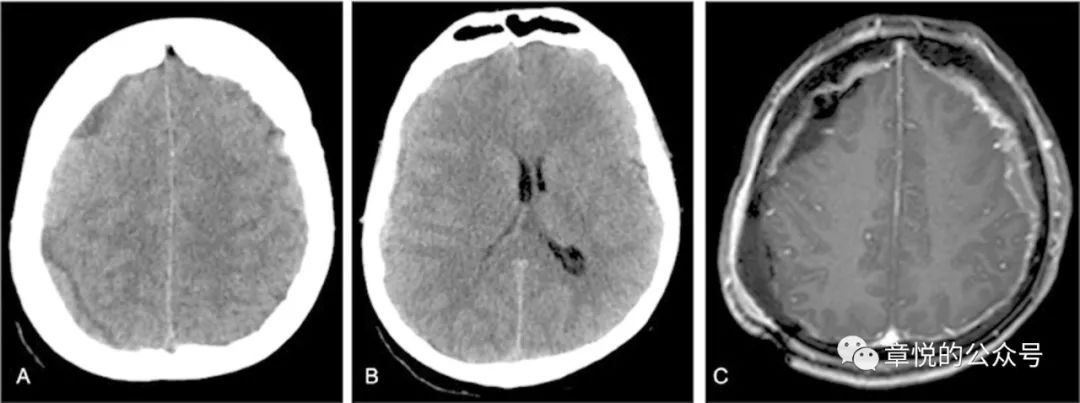

我今天讲述的这例慢性硬膜下血肿由急性者迁延所致,3个月来血肿没有大变化(图1),然而临床症状却突然加重了。

图1. 患者3个月来硬膜下血肿始终没有吸收,1个月前血肿影密度较前增高。

患者老年男性,3个月车祸头部受伤,当时除头痛没有其他症状,到当地医院行CT见左侧硬膜下血肿,因出血量不大,所以神经外科建议保守治疗,3个月中患者几次CT未见血肿吸收,但也没觉得什么不适。1周前患者开始出现头晕和左侧头痛,之后逐步出现意识混乱,言不达意,在入院前2天出现癫痫频繁发作,一天发作几十次,但头颅CT上血肿量并无增多,神经外科仍建议继续保守治疗。

入院后予丙戊酸钠、左乙拉西坦和妥泰抗癫痫治疗,但住院3天患者依旧每天都有癫痫发作,表现为双眼向右侧视,头向右侧转,意识丧失,每次数分钟,发作间期意识模糊,萎靡不振,最多只能说出两三个字,行头颅MRI见左侧硬膜下血肿,并可见左侧颞枕叶肿胀,T2,FLAIR及DWI为略高信号。(图2)腰穿压力生化常规正常。

图2.FLAIR相左侧颞枕叶肿胀,信号增高